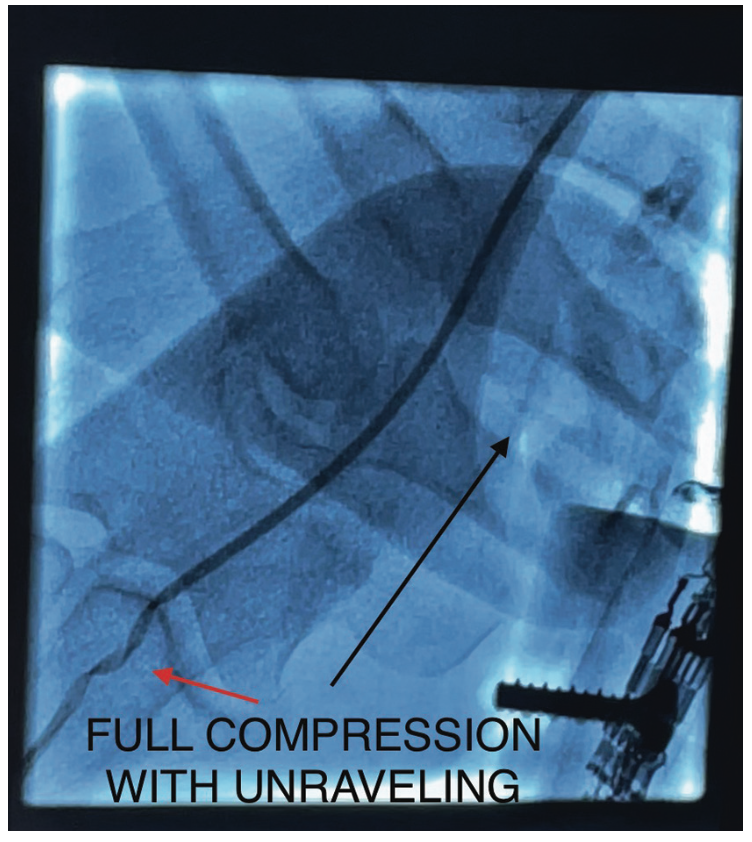

Unfortunately, the technologist would need to be close to the radiation source in order to help the patient, as well as have both hands in the primary radiation beam. After convening, we decided to attempt this technique with the use of minimal intermittent fluoroscopy and proper radiation protection. Regrettably, we did not have lead gloves available (which may or may not help with shielding, being in the primary beam). Under fluoroscopy, the kink was moved to the distal brachial artery very carefully while confirming the patient did not have pain in the arm. Once the catheter reached the distal brachial artery, under fluoroscopy, the technologist compressed the brachial artery with significant pressure proximal to the kink (Figures 3-4). The attending physician un-torqued and simultaneously pulled the catheter (Figure 5). Within seconds, we resolved the issue safely and efficiently. We aborted the RRA access site, cannulated the left distal radial artery (Figure 6), and completed the case.